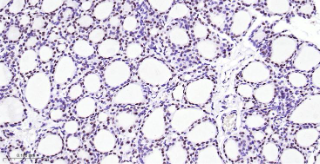

Immunohistochemical analysis of paraffin embedded rat thyroid gland tissue slide using IHC0477R (Rat TTF1/NKX2-1 IHC Kit).